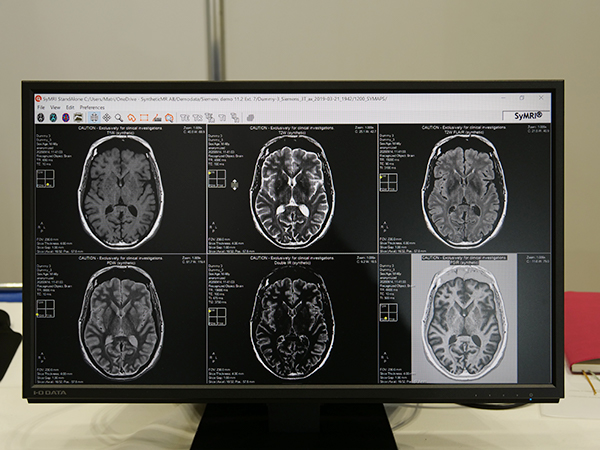

MDMEを用いることで,SyMRI NEUROでは1回約6分の撮像で,9種類のコントラスト強調画像を取得できる。9種類の画像は,T1WI,T2WI,T1W FLAIR,T2W FLAIR,PDWI,T2W STIR,PDW STIR,double IR,PSIR。これにより,大幅に撮像時間を短縮でき,検査のスループットが向上する。また,複数回撮像を行うと,被検者の体動によって位置ズレが生じるが,それを回避できる。撮像時間の短縮は,被検者の負担軽減にもつながる。特に,小児や高齢者など長時間の静止が困難な被検者の検査においては有用である。さらに,撮像後にもTR,TE,TIのパラメータを調整でき,コントラストの変更が可能である。

「SyMRI NEURO」で取得可能なマルチコントラスト強調画像